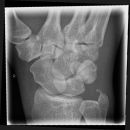

Handgelenk a.p.

Beurteilungskriterien

- Neigung der distalen Radiusgelenkfläche in der Frontalebene: 15 – 35°

- Längenverhältnis Radius – Ulna: Proc.styloideus radii überragt Gelenkfläche der Ulna um 9 –12mm (<9mm Ulna-Plusvariante, >12mm Ulnaminusvariante)

- Kontinuität der drei Karpalbögen:

Proximaler Bogen: proximale Gelenkflächenkonturen von Scaphoid, Lunatum und Triquetum

Mittlerer Bogen: distale Gelenkflächenkonturen von Sacphoid, Lunatum und Triquetum

Distaler Bogen: proximale Gelenkflächenkonturen von Capitatum und Hamatum

Fehlende Abgrenzbarkeit, Versatz oder Unterbrechung sind als pathologisch zu bewerten und deuten auf eine Luxation hin.

Trapezförmige Darstellung des Lunatum in Neutralstellung? Augenzeichen des Hamulus? Superposition von Pisiforme und Triquetum? Metacarpale III in Projektion innerhalb der Radiusgelenkfläche? Lunatum zu >50% über Radiusgelenkfläche? Cave: bei Radial- oder Ulnarduktion wandert das Lunatum in umgekehrter Richtung.

- M-förmiger Verlauf der Gelenkspalten der Carpometacarpalgelenke? Luxationsstellung in den Carpometacarpalgelenken (meist dorsale Luxation)?

- Gelenkspaltweiten des Radiocarpalgelenk 2 – 2,5mm, der Carpometacarpalgelenke 1 –2mm, distales Radioulnargelenk 2mm, Gelenksspaltweiten der Intercarpalgelenke 1,5 – 2mm

Cave: SL-Dissoziation (Ruptur des SL- Bandes, häufigste Gefügestörung): Terry-Thomas-Sign = SL-Spalt > 3mm, Siegelringzeichen = Ringförmige Transparenzminderung im mittleren Scaphoiddrittel durch orthograde Projektion der Taille infolge Rotation.

- Obliteration des Scaphoidfettstreifens?

- Täuschungsmöglichkeiten durch Vielzahl akzessorischer Ossikel (abgerundete, zirkulkär-geschlossene Kortikalis), geteilte Handwurzelknochen (Scaphoid, Lunatum, Pisiforme) und Gefäßkanälchen

- Target areas leicht zu übersehender Frakturen: distales Radioulnargelenk, Processus styloideus radii et ulnae, Basen der Metacarpalia (v.a. MCP I), Hamulus.

- Grundsätzlich gilt: unklare Verhältnisse ->CT-Indikation